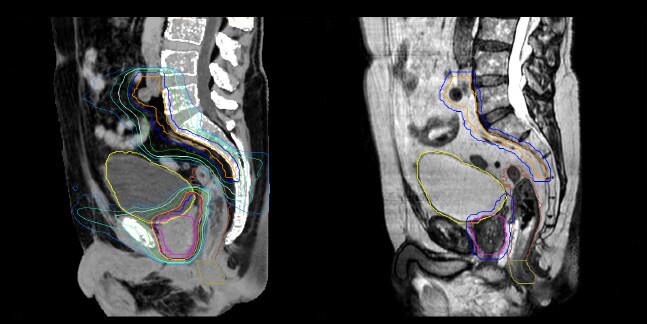

Dose plans overlaid on CBCT image dataset (left) and on MRCAT image dataset (right).

Dosimetric equivalence validation was performed on 43 patient cases by comparing MRCAT-based dose plans overlaid on CBCT image dataset and on the corresponding MRCAT image dataset. Mr. Bolard and Dr. Champion found good agreement between MRCAT-based and CT-based dose calculations, with a mean dose ratio of 1.007 (0.991-1.014). The 3D gamma score was greater than 95% (95.2-99.0%) for all plans checked. A poster on this work was accepted for presentation at ESTRO 2020.

Evaluation of MRCAT dosimetric accuracy

Mr. Bolard and Dr. Champion found good agreement between MRCAT-based and CT-based dose calculations, with a mean dose ratio of 1.007 (0.991-1.014).